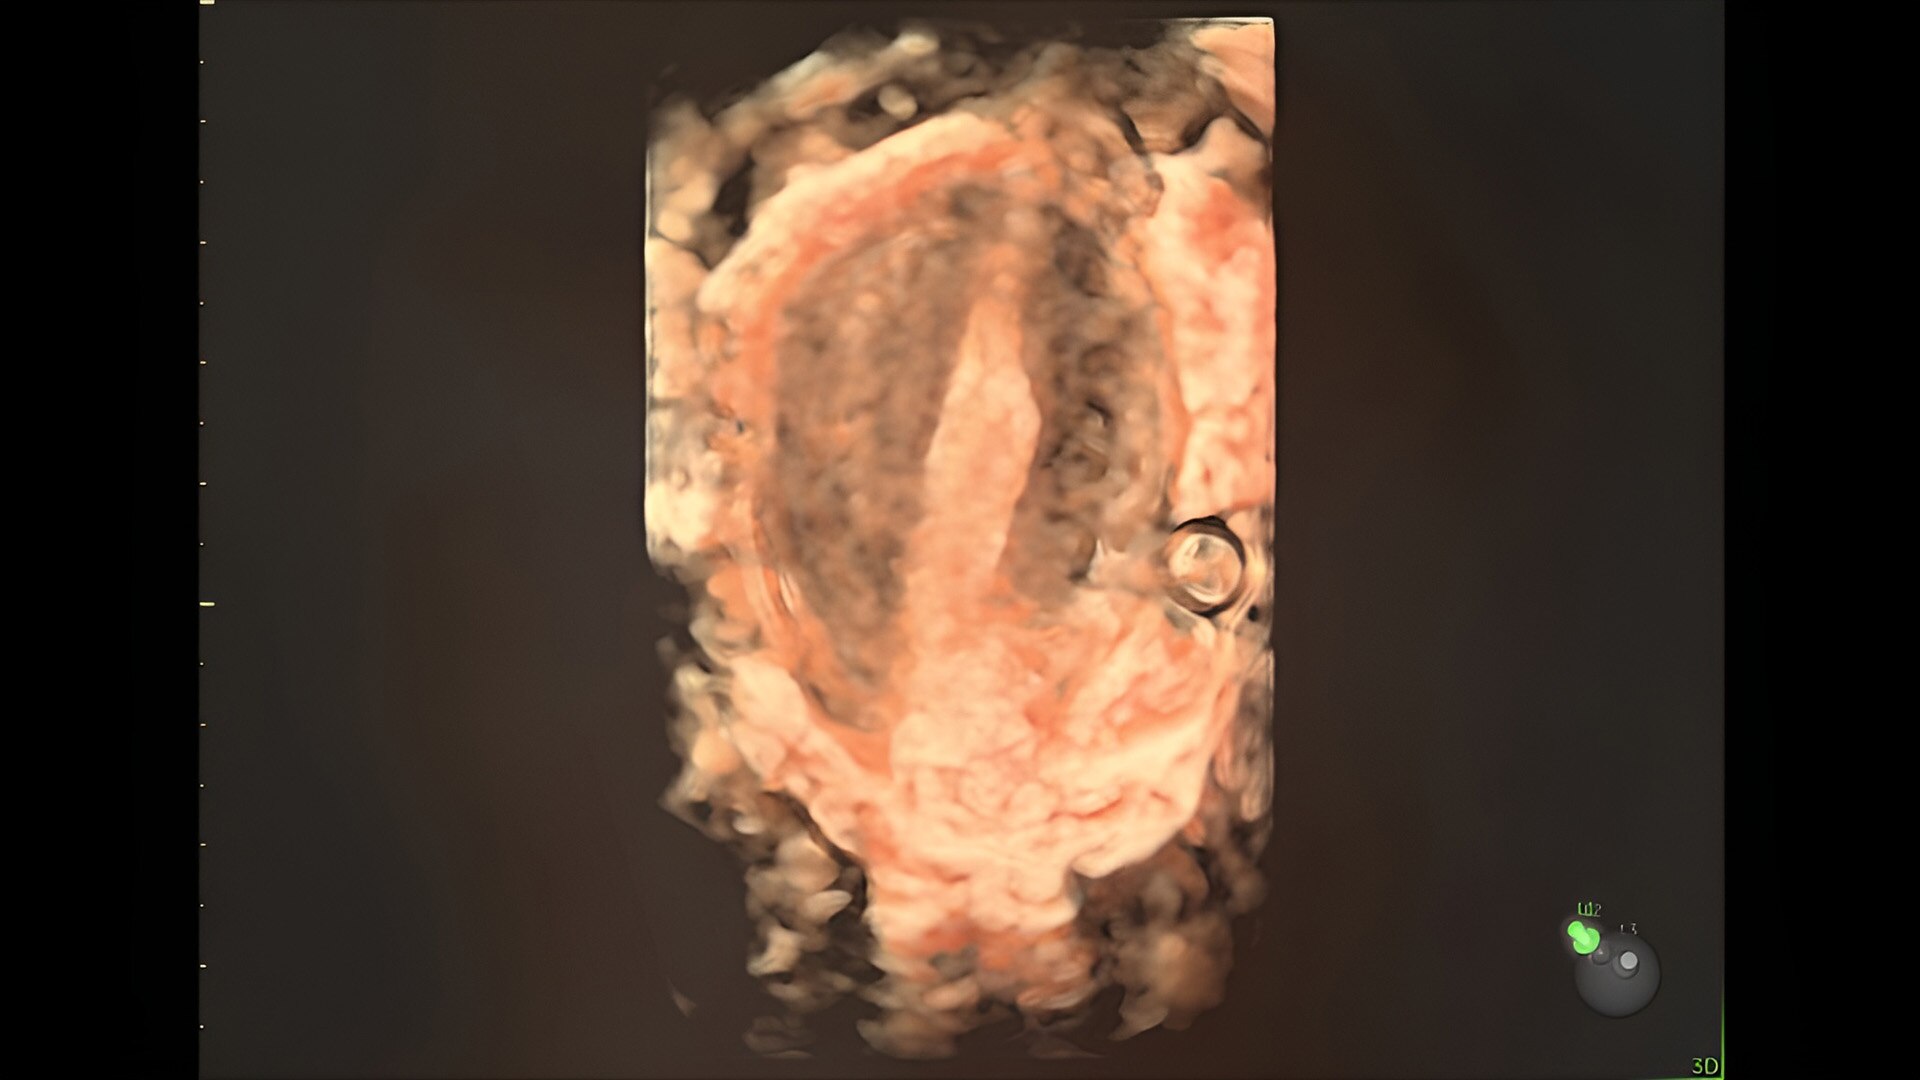

Fetal heart evaluation

Get to the heart of the matter

Identifying fetal cardiac abnormalities earlier means you can intervene sooner, plan for delivery, and potentially improve outcomes. The Voluson Expert 22 provides a full solution of progressive tools, to help distinguish the tiniest structures with stunning clarity to provide patient answers faster.